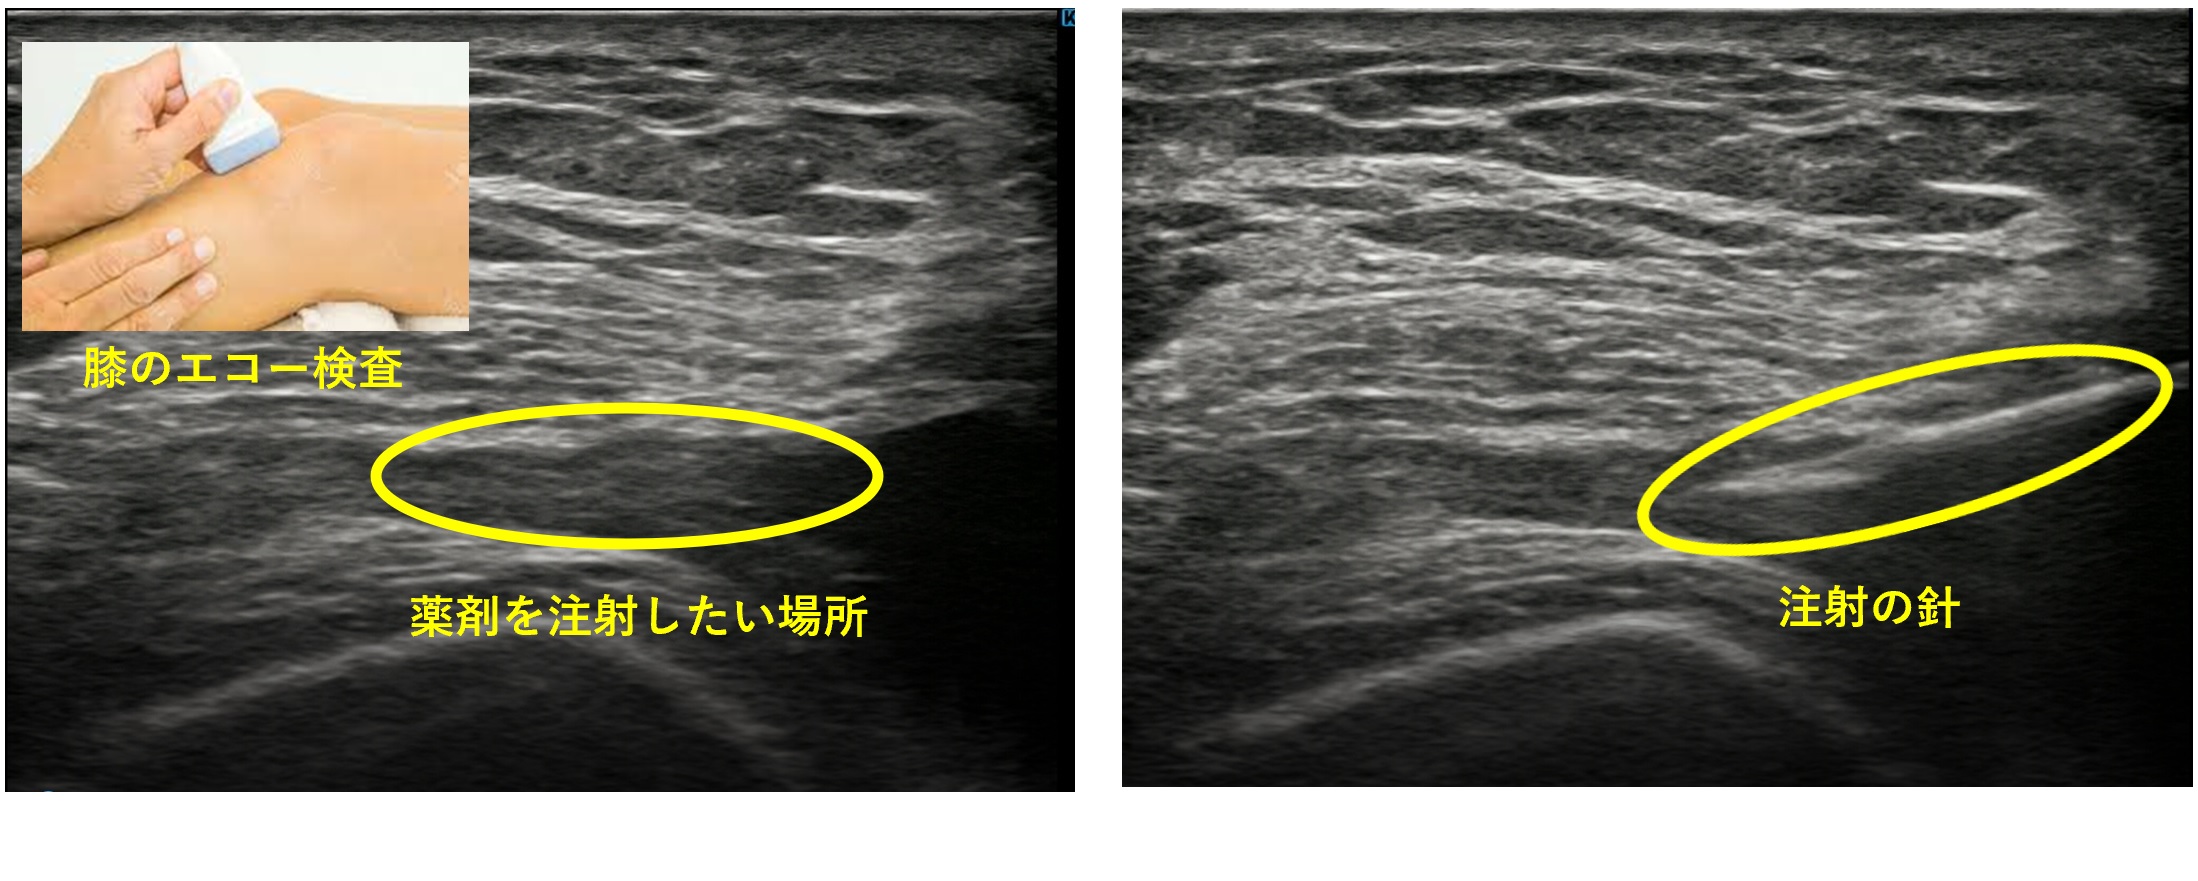

超音波検査(エコー)

X線検査では評価しにくい、靭帯、筋肉、腱などの組織をより正確に評価します。

また、針先を見ながら注射をすることで、より正確に患部に薬剤を投与するなど、診断だけではなく治療にも役立てています。

身体への侵襲がなく安心して何度も検査を受けていただくことが可能です。